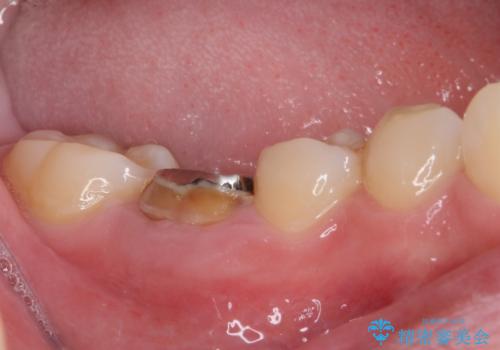

- 放置した虫歯や抜いたままの奥歯、前歯のデコボコを気にして来院された患者様です。

口元の突出感は少なく、下顎の叢生は軽微なものであったので、叢生の強い上顎左右の小臼歯を1本ずつ抜歯し、ワイヤー装置にて矯正治療を行うこととしました。

矯正治療を行う前に、根管治療の必要な上顎前歯と下顎大臼歯の根管治療を行い、矯正治療の途中で下顎の欠損部にインプラント埋入することとし、矯正治療後に補綴治療を行うこととしました。